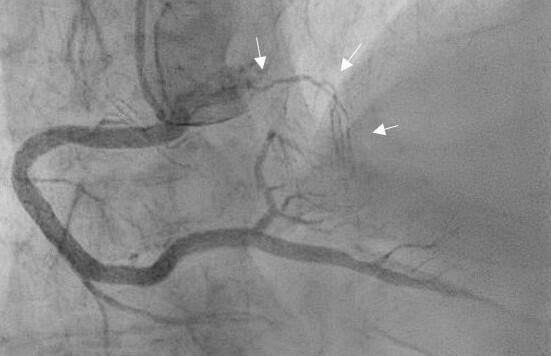

A 71-year-old man with a medical history of diabetes, hypertension, and smoking presented to the emergency department because of acute retrosternal pain. An electrocardiogram (ECG) recorded left anterior fascicular block, right bundle branch block, and ST-segment elevation in leads V3 to V5 without reciprocal changes (Figure A). Urgent coronary angiography demonstrated a descending septal artery, also known as Bonapace’s branch, arising from the proximal right coronary artery (Figure B, Video 1), and a totally occluded left anterior descending artery (LAD) in the mid-segment (Figure C, Video 2).

Bonapace’s branch, though an infrequent anatomical variation, provides valuable collateral circulation to the interventricular septum, atrioventricular node, and His bundle during acute or chronic occlusion of the LAD, especially in the absence of a well-developed first septal branch. In our patient, collateral blood supply through Bonapace’s branch to the acutely occluded LAD reduced the ischemic consequences, as shown by the absence of reciprocal ECG changes, moderate elevation in hsTn, and preserved EF at discharge.